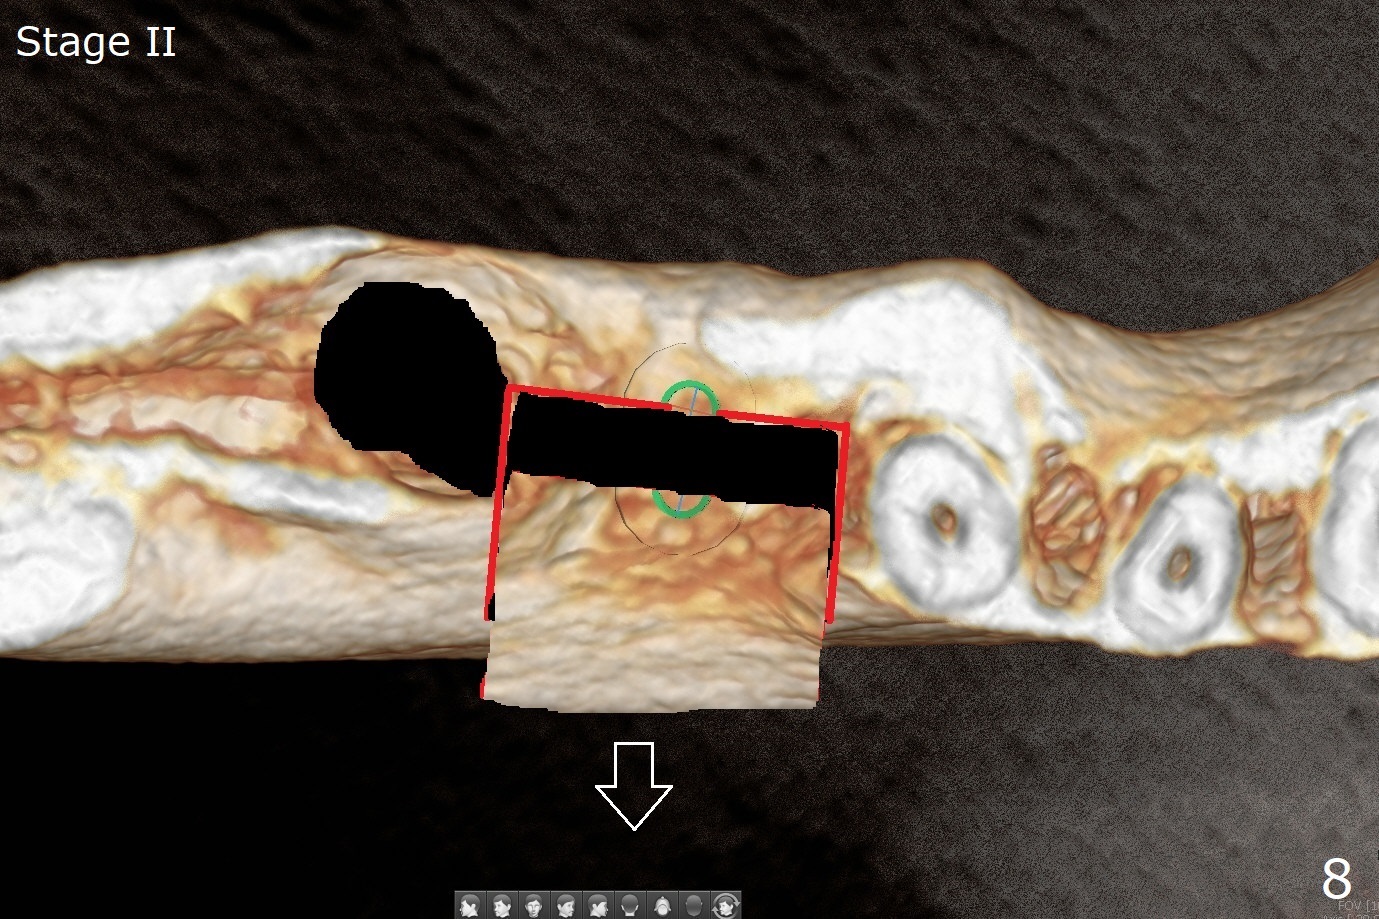

Several months post #31 socket preservation, the narrow ridge of #30 (Fig.1 (CT 3-D occlusal view), 6 (coronal section)) will be exposed with a crestal and 2 oblique incisions, followed by osteotomy with a 2 (2.2) mm drill (green) and a surgical guide. A crestal transverse cut will be conducted using a surgical fissure bur (Fig.2 red), followed by 2 vertical cuts (Fig.3,4 (3-D X-ray mode, buccal view) and an apical transverse one (Fig.5,6). The incision will be closed. Three weeks later, a crestal incision will be made. The buccal plate will be fractured and pushed buccal (Fig.7,8 arrow) using chisel (yellow). The guide will be reseated for osteotomy, implant placement (Fig.9 green) and bone graft. In fact there is not much problem when the osteotomy moves lingual.